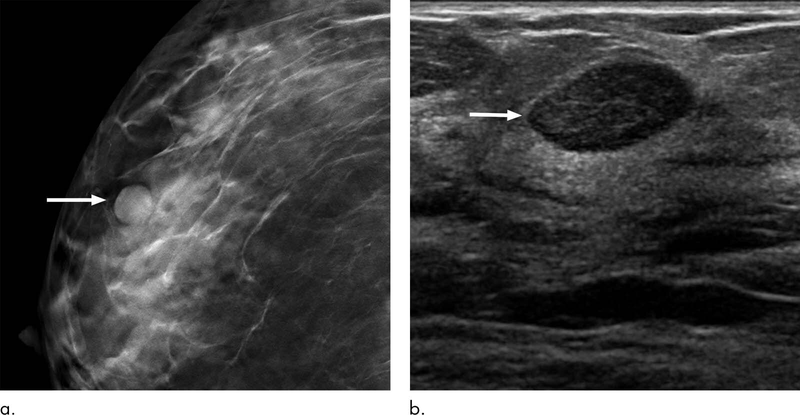

BI-RADS 2 Là Gì? Ý Nghĩa Và Cách Xử Lý Khi Nhận Kết Quả BI-RADS 2

BI-RADS 2 là gì? Đây là một trong các cấp độ được sử dụng trong hệ thống phân loại hình ảnh vú BI-RADS, giúp đánh giá nguy cơ ung thư vú qua các...